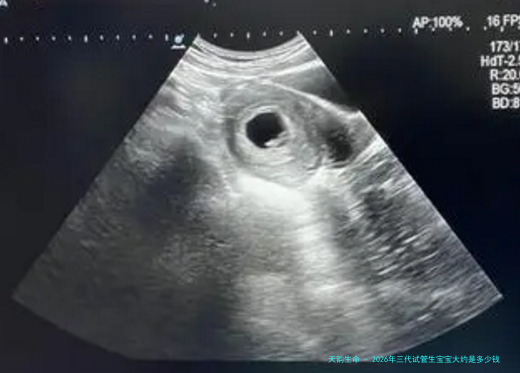

医疗费:包括妇科检查、男性精液检查、超声波监测等项目,大约需要十万块。